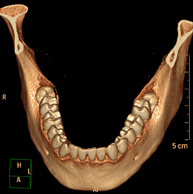

- Dental CT

Radiological test that provides high definition anatomical images of the maxillary bone (teeth, dental nerve path) using CT (Computed Tomography) equipment. Indicated for: examination prior to dental extraction, examination prior to implants, tumours, abscess.